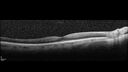

Stable Myopic Tractional Maculopathy30 views73 year old female with mild vision loss from table myopic tractional maculopathy in the left eyeNov 23, 2025

Stable Myopic Tractional Maculopathy23 views73 year old female with mild vision loss from table myopic tractional maculopathy in the left eyeNov 23, 2025

Stable Myopic Tractional Maculopathy32 views73 year old female with mild vision loss from table myopic tractional maculopathy in the left eyeNov 23, 2025

Stable Myopic Tractional Maculopathy22 views73 year old female with mild vision loss from table myopic tractional maculopathy in the left eyeNov 23, 2025

Stable Myopic Tractional Maculopathy21 views73 year old female with mild vision loss from table myopic tractional maculopathy in the left eyeNov 23, 2025

Stable Myopic Tractional Maculopathy18 views73 year old female with mild vision loss from table myopic tractional maculopathy in the left eyeNov 23, 2025

Stable Myopic Tractional Maculopathy14 views73 year old female with mild vision loss from table myopic tractional maculopathy in the left eyeNov 23, 2025

Stable Myopic Tractional Maculopathy16 views73 year old female with mild vision loss from table myopic tractional maculopathy in the left eyeNov 23, 2025